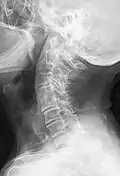

-

Block vertebrae of the cervical spine (vertebrae 4 and 5). Probably based on degenerative or inflammatory changes. -